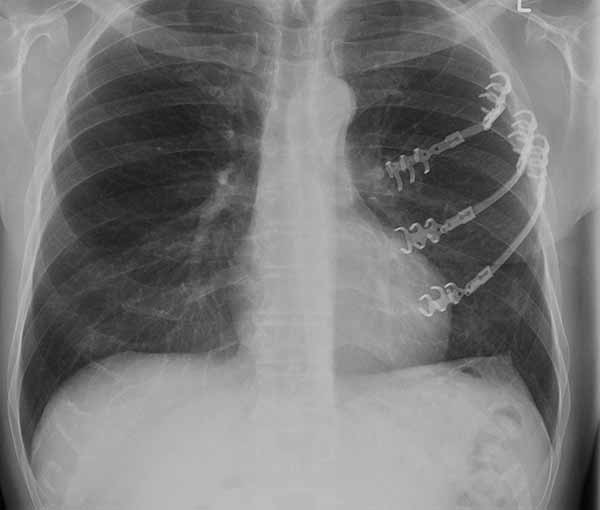

- Chest wall resection for malignancy (Figures 4-5)

| Figure 4: Model showing application in chest wall resection. | Figure 5: Postoperative chest x-ray showing the implants |